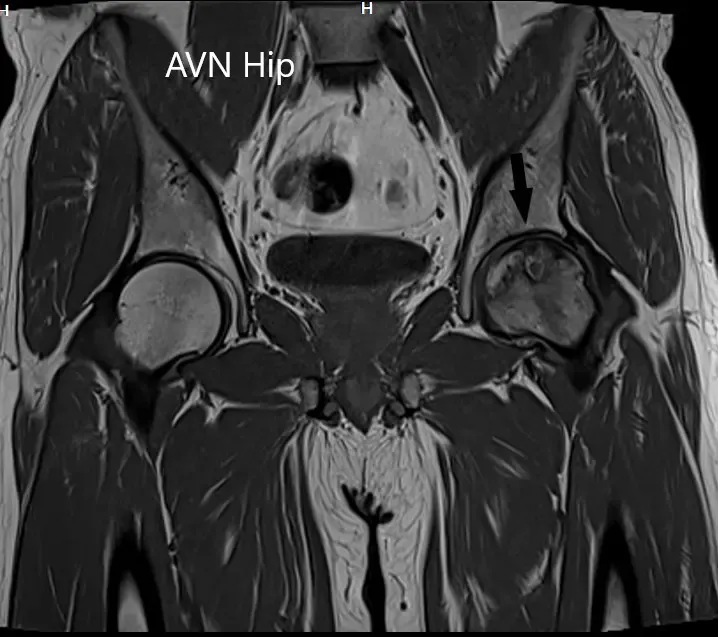

Se realizó una resonancia magnética que sugirió necrosis avascular de la cadera izquierda, estadio 3. Hubo una intensidad alterada de la señal y edema de médula ósea.

Sección coronal T1WI de la resonancia magnética que muestra AVN en cadera.